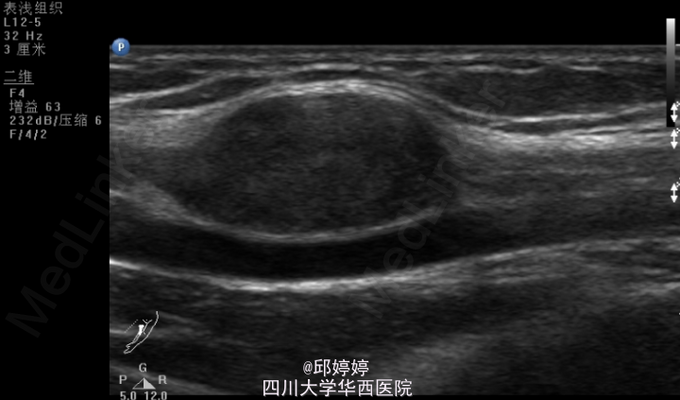

视:左上臂无明显畸形及肌萎缩,肌力5级。无色斑、窦道。触:左上臂近端肱二头肌内侧正中神经可摸及约蚕豆大小的肿物,压痛,并向左上肢及中指放射,活动度不大,与正中神经粘连,Tinner征阳性。动量:左肩、肘、腕关节活动自如。辅助检查:左上肢包块彩超:左上臂包块处查见大小约25*11*16mm的弱回声团,边界清楚,该团块与正中神经相连,内未见明显血流信号(图1,2)。超声诊断提示:左上臂实性团块:神经源性肿瘤?